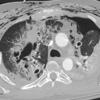

laceration

Date: 07/26/2006

Views: 4516